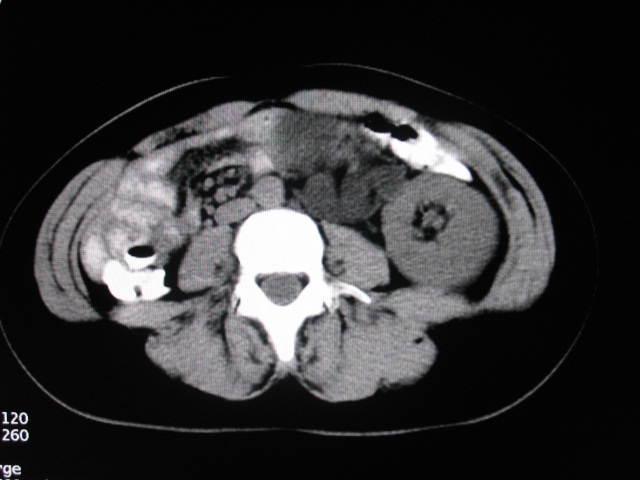

女,28岁,自觉腹部包块一年余

左侧为扩张的输尿管,一直延续到膀胱,那么它的上端应该是扩张的肾盂,但是在他的下方我们看到一个比较正常的肾,所以考虑左侧重复肾盂输尿管畸形。

考虑左侧双肾盂双输尿管畸形,其中一输尿管末端梗阻(不排除异位开口可能)并相应之肾盂及输尿管明显扩张积水。

考虑右肾发育不良,左侧巨输尿管畸形并肾积水。

术后证实是左侧双肾盂双输尿管畸形,巨输尿管巨肾盂症